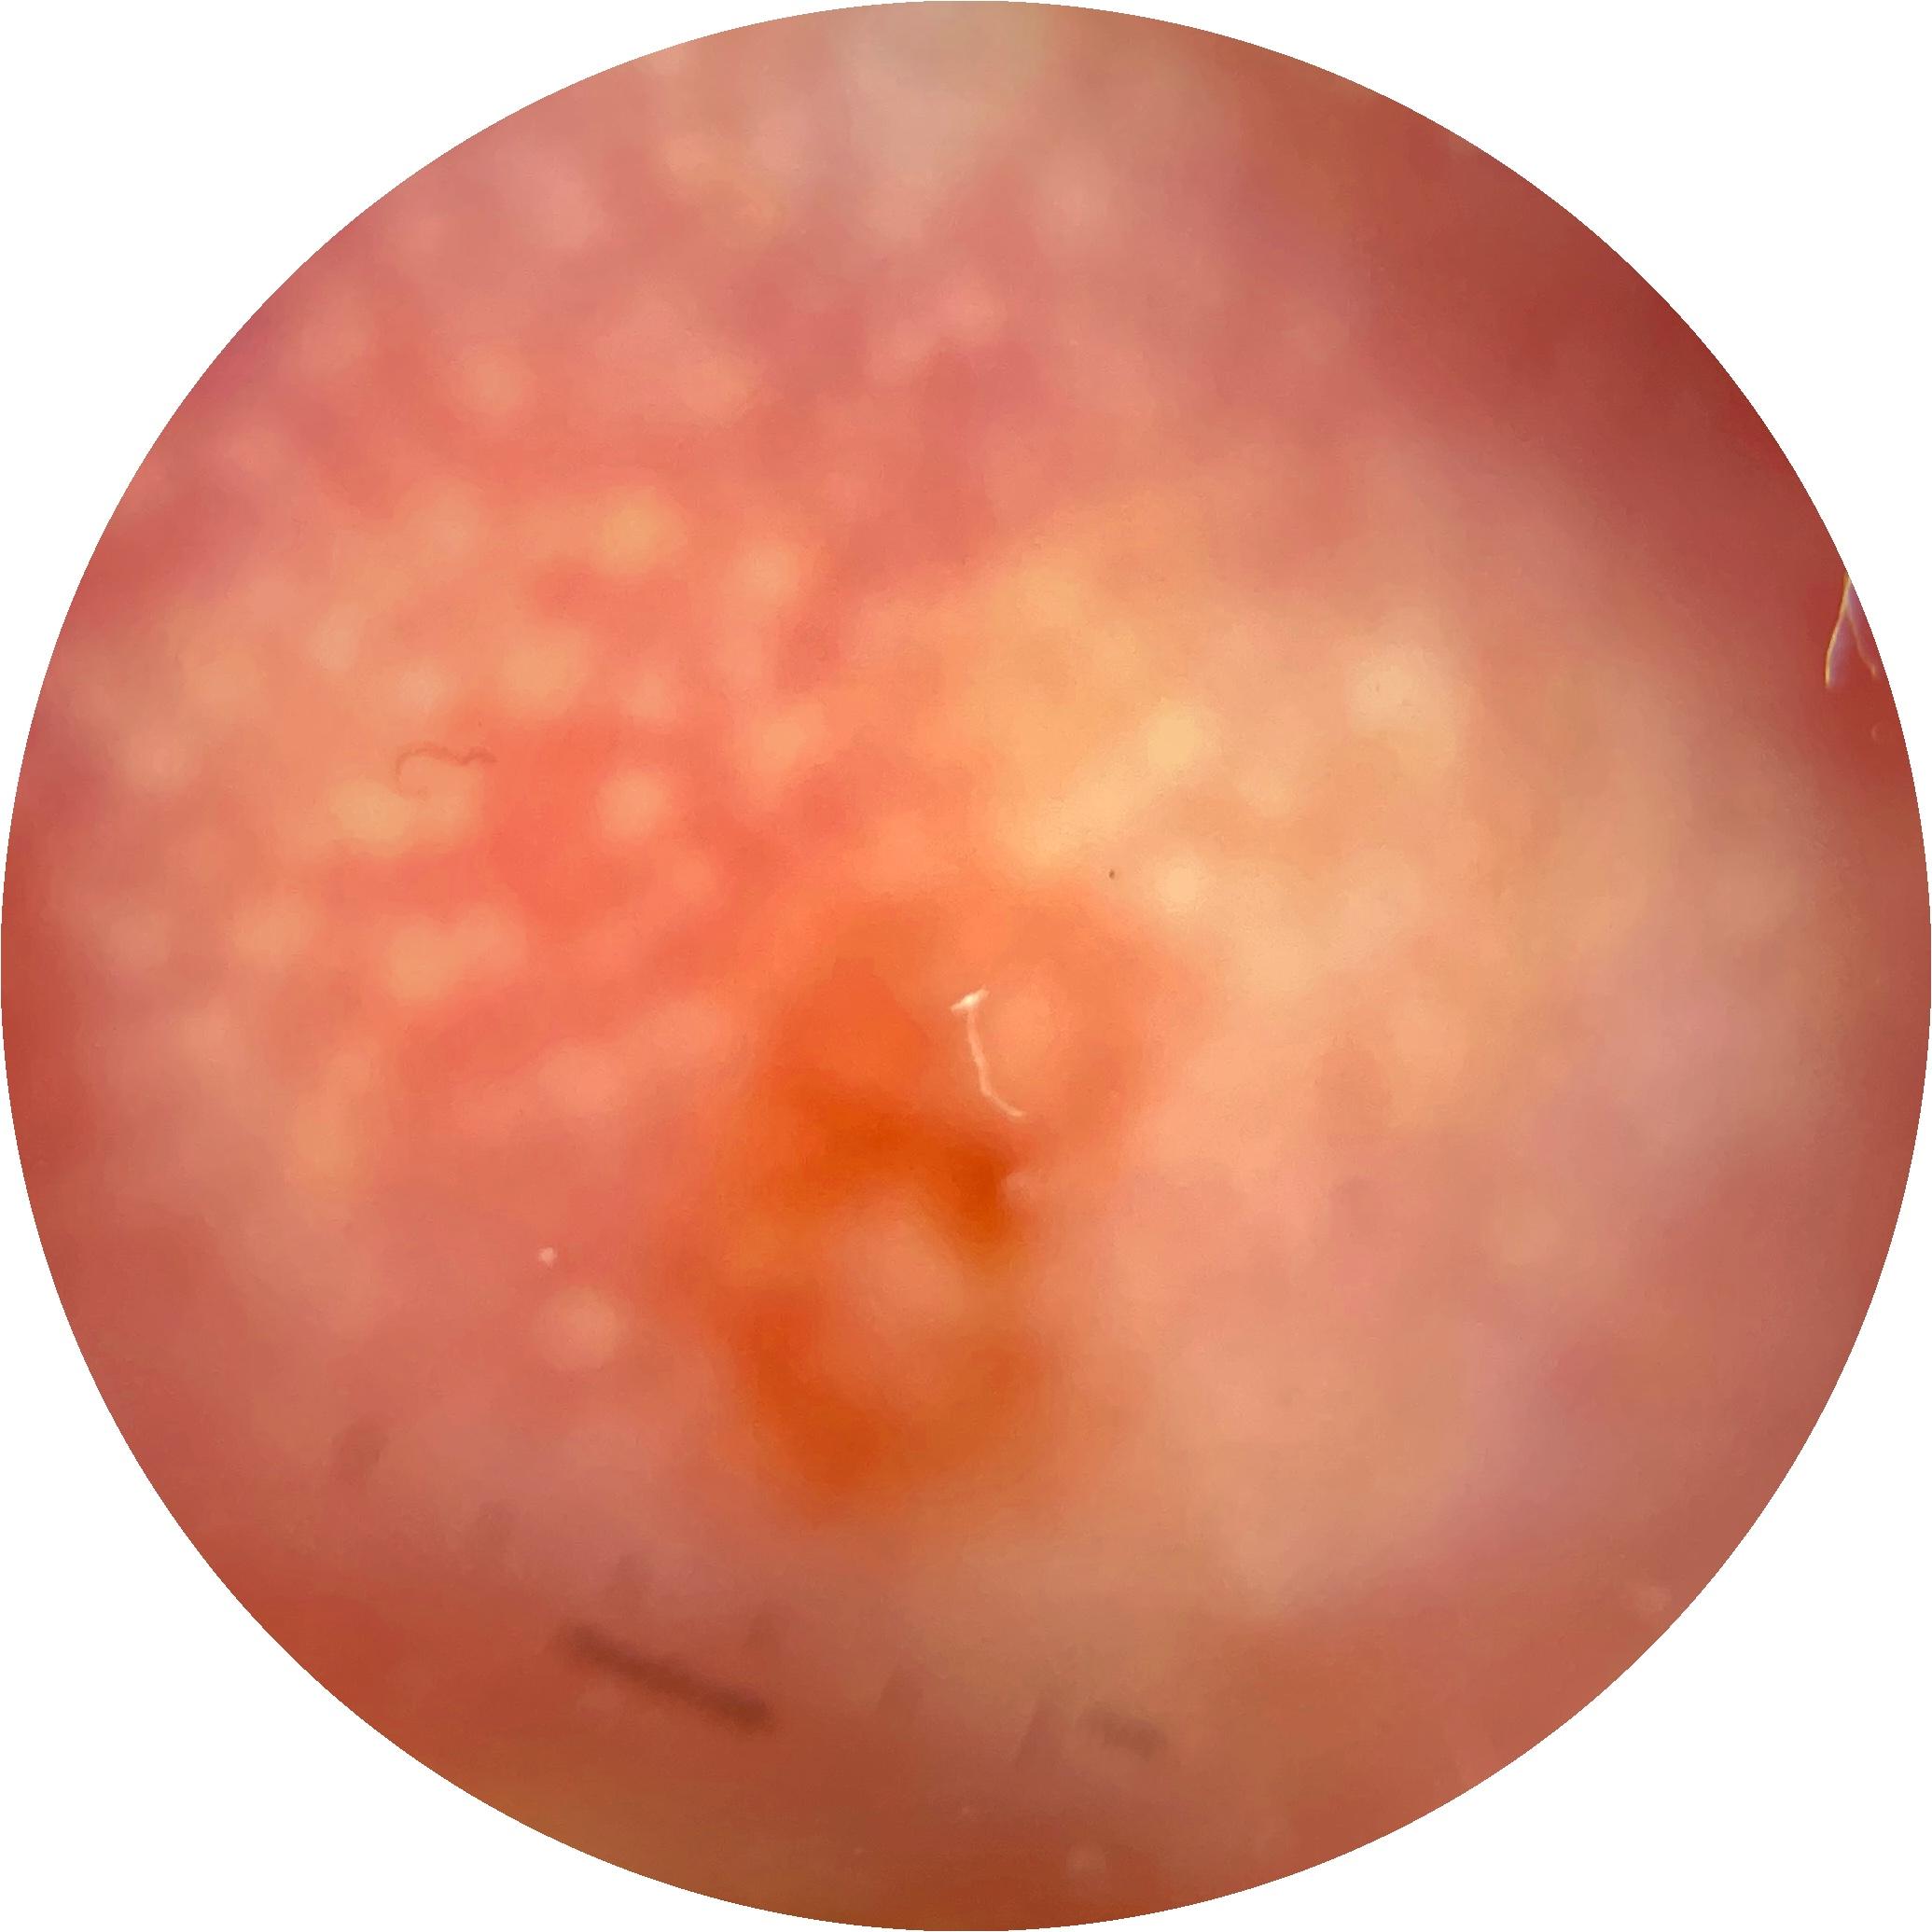

ISIC_9785574

Clinical

Field Value

acquisition_day 148

age_approx 45

anatom_site_1 Head and neck

anatom_site_general head/neck

concomitant_biopsy False

diagnosis_1 Benign

diagnosis_confirm_type single image expert consensus

family_hx_mm True

image_manipulation instrument only

image_type dermoscopic

lesion_id IL_0236417

patient_id IP_8456088

personal_hx_mm True

sex female